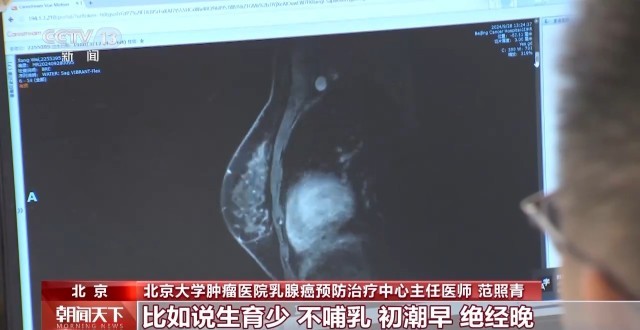

北京大学肿瘤医院乳腺癌预防治疗中心主任医师

范照青

:乳腺癌的发病的高危因素,包括了比如说一些基因的突变,乳腺癌的家族史,既往胸部经受过放疗;还有一些是跟生活方式有关的,比如说生育少,不哺乳,初潮早,绝经晚,还有肥胖、酗酒、不参加体育活动等等。, 据了解,